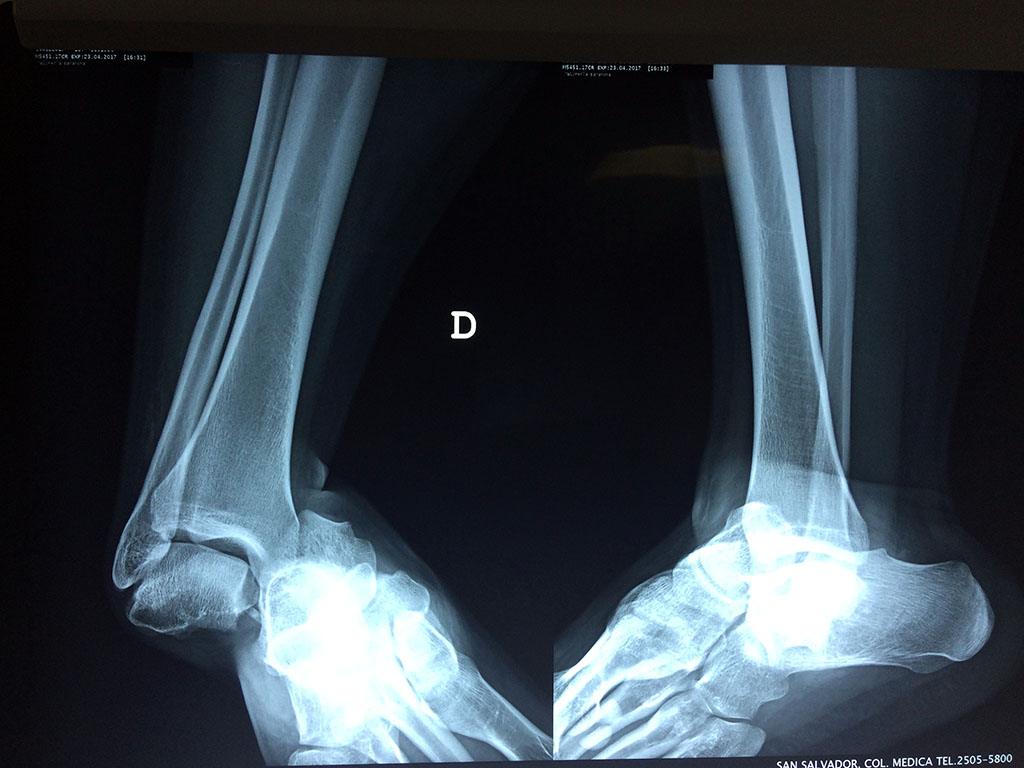

Una fractura de tobillo es la rotura de uno o más de los huesos del tobillo. Estas fracturas pueden ser:

- Producirse en uno o ambos lados del tobillo.

Algunas fracturas de tobillo pueden requerir cirugía si:

- Los extremos de los huesos están desalineados entre sí (desplazados).